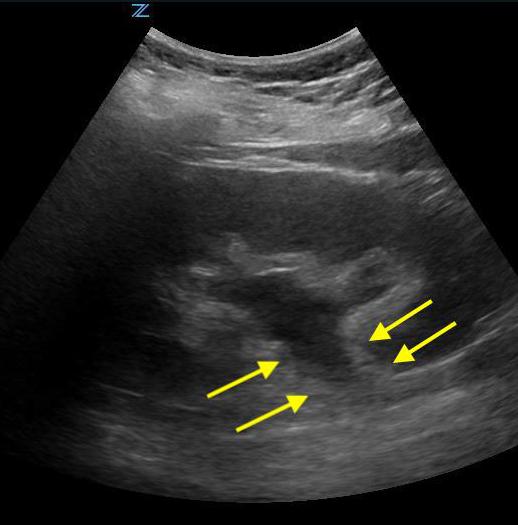

- Figure 2. Moderate hydronephrosis demonstrating location of ureter (surrounded by arrows) exiting renal pelvis

- The ureters are generally not well visualized by US, but, when distended may appear as a tubular structure extending inferiorly from the kidney

- Videos 14-15. Moderate hydronephrosis

Video 16. Moderate to severe hydronephrosis